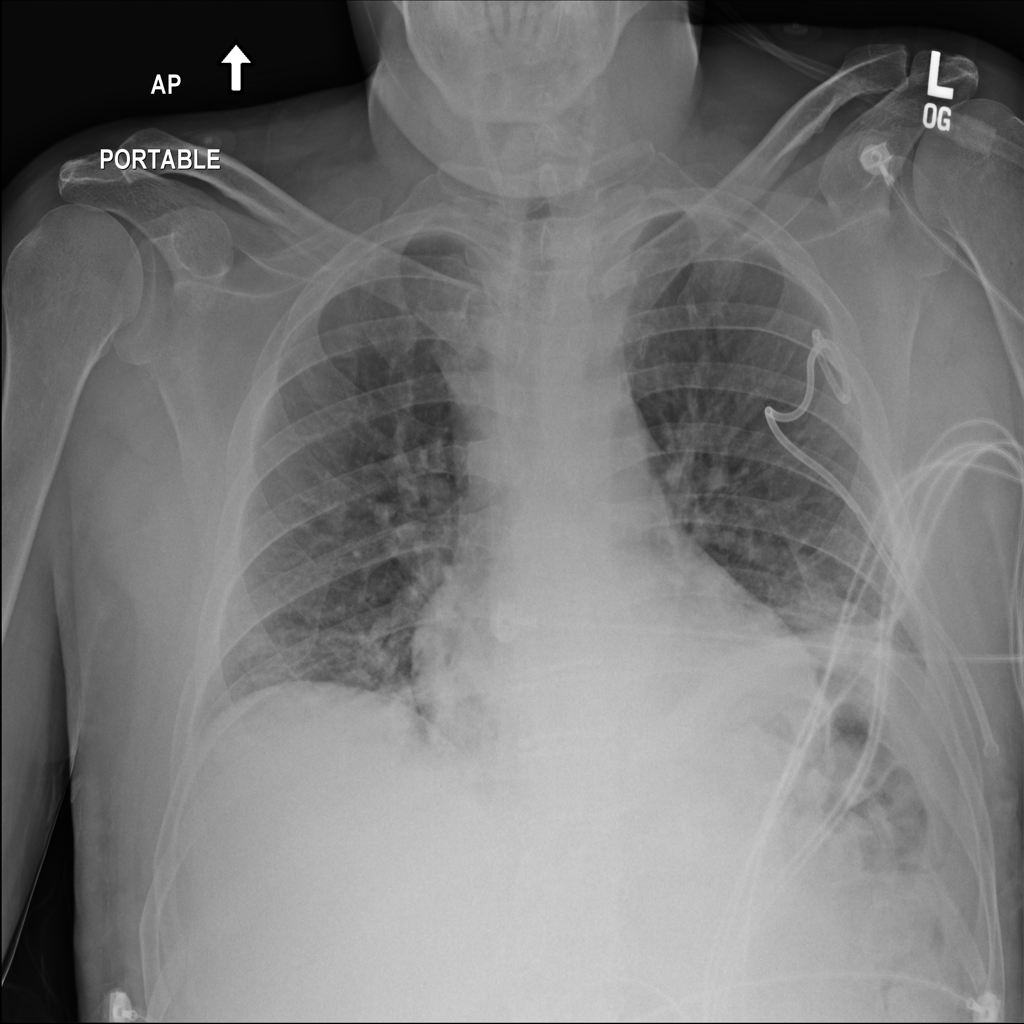

PAT-299B · IMG-003Atelectasis

PAT-299B · IMG-003

AP